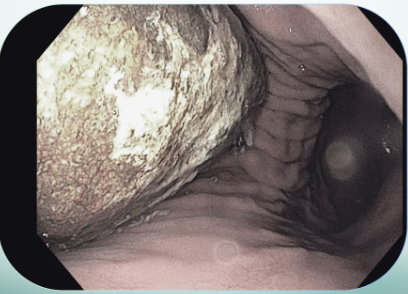

Bệnh viện Đa khoa Hồng Ngọc vừa nội soi can thiệp lấy bã thức ăn "khổng lồ" 15cm trong dạ dày cụ bà 85 tuổi thích ăn hồng ngâm.

Theo đó, cụ bà H.T.V (85 tuổi) nhập viện trong tình trạng đau bụng dữ dội kèm sốt cao kéo dài suốt 1 tuần. Qua nội soi dạ dày, bác sĩ Bệnh viện Đa khoa Hồng Ngọc phát hiện khối bã thức ăn lớn, kích thước 10 x 15cm trong dạ dày, xung quanh có các ổ viêm, ổ loét khoảng 2cm.

Khối bã thức ăn "khổng lồ" 15 cm trong dạ dày - Ảnh BVCC